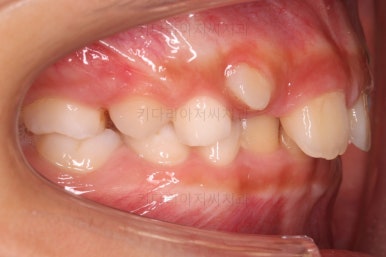

전후사진을 비교해 보겠습니다.

왼쪽이 부산어린이돌출입교정 치료 전, 오른쪽이 치료 후 입니다.

위치가 나빴던 앞니가 제위치로 갔고, 위아래 앞니도 서로 가까워졌어요.

앵글씨 2급 부정교합이 개선된거죠.

아래턱-위턱이 차이날 때 필연적으로 생기는 과개교합(앞니가 서로 깊게 맞물리는 교합)도 개선되었고요.

입이 튀어나와 보이던 모습도 완벽히 개선되었어요.

아래턱이 작아보이던 모습독 개선되었고 입도 편안하게 다물어져요.

턱의 위치가 잘못되어 결과적으로 보이던 "입이 튀어나온 모습, 윗니가 튀어나온 모습"이 턱뼈의 위치를 바로 잡아줌으로써 개선이 된거죠.